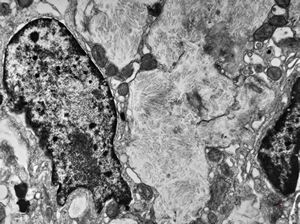

Whipple disease - lipid malabsorption

jejunum … lipid malabsorption